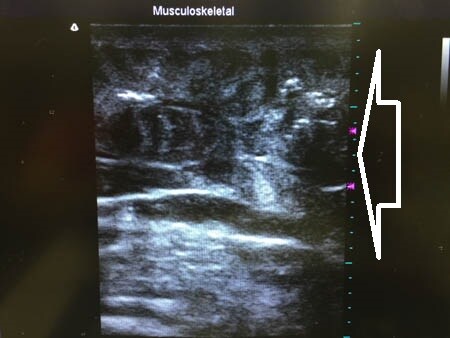

上の画像の部分の皮下脂肪層をつまんでみましょう。

↓ ↓ ↓

同様に右二の腕。 ↓ ↓ ↓